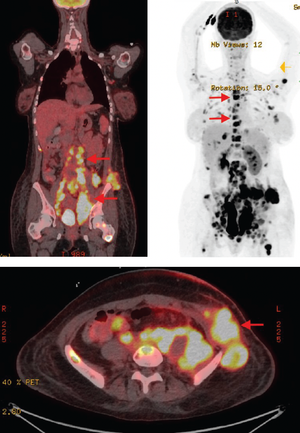

Unusual Clinical Presentation of Clear Cell Sarcoma in a Young Woman

A young woman presents with painless lumps to the emergency department and is later diagnosed with clear cell carcinoma.